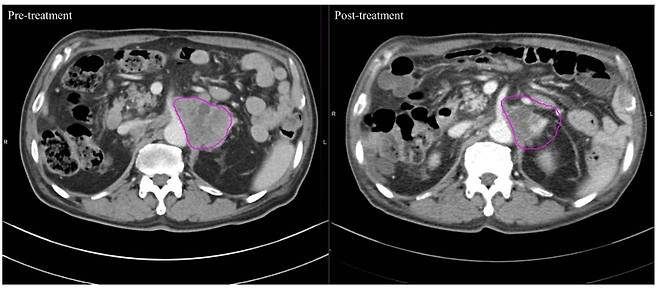

24일 국제바이러스연구연합(IVRA) 조직위원회에 따르면 장홍석 서울성모병원 방사선종양학과 교수 연구팀은 2019년 1월부터 2022년 3월 말까지 고온 온열치료 환자 20명과 방사선 단독 치료 환자 20명 등 전이성 복부 림프절 치료 환자 총 40명을 대상으로 컴퓨터 단층촬영(CT) 이미지를 모았다. 그리고서 치료 전후 종양 괴사의 변화를 관찰하는 지표(하운스필드 단위·Hounsfield Unit·HU)값의 변화를 비교해 치료 효과를 평가했다.

그랬더니 고온 온열치료 그룹은 치료 후 HU 값이 평균 9.05%(-8.47HU) 낮아진 58.95로 나타났다. 반면 기존의 방사선 치료 그룹은 0.57%만 줄어든(-0.41HU) 71.42였다. 이번 연구 결과는 최근 국제학술지 '플러스 원(PLOS ONE)'에 발표됐다.